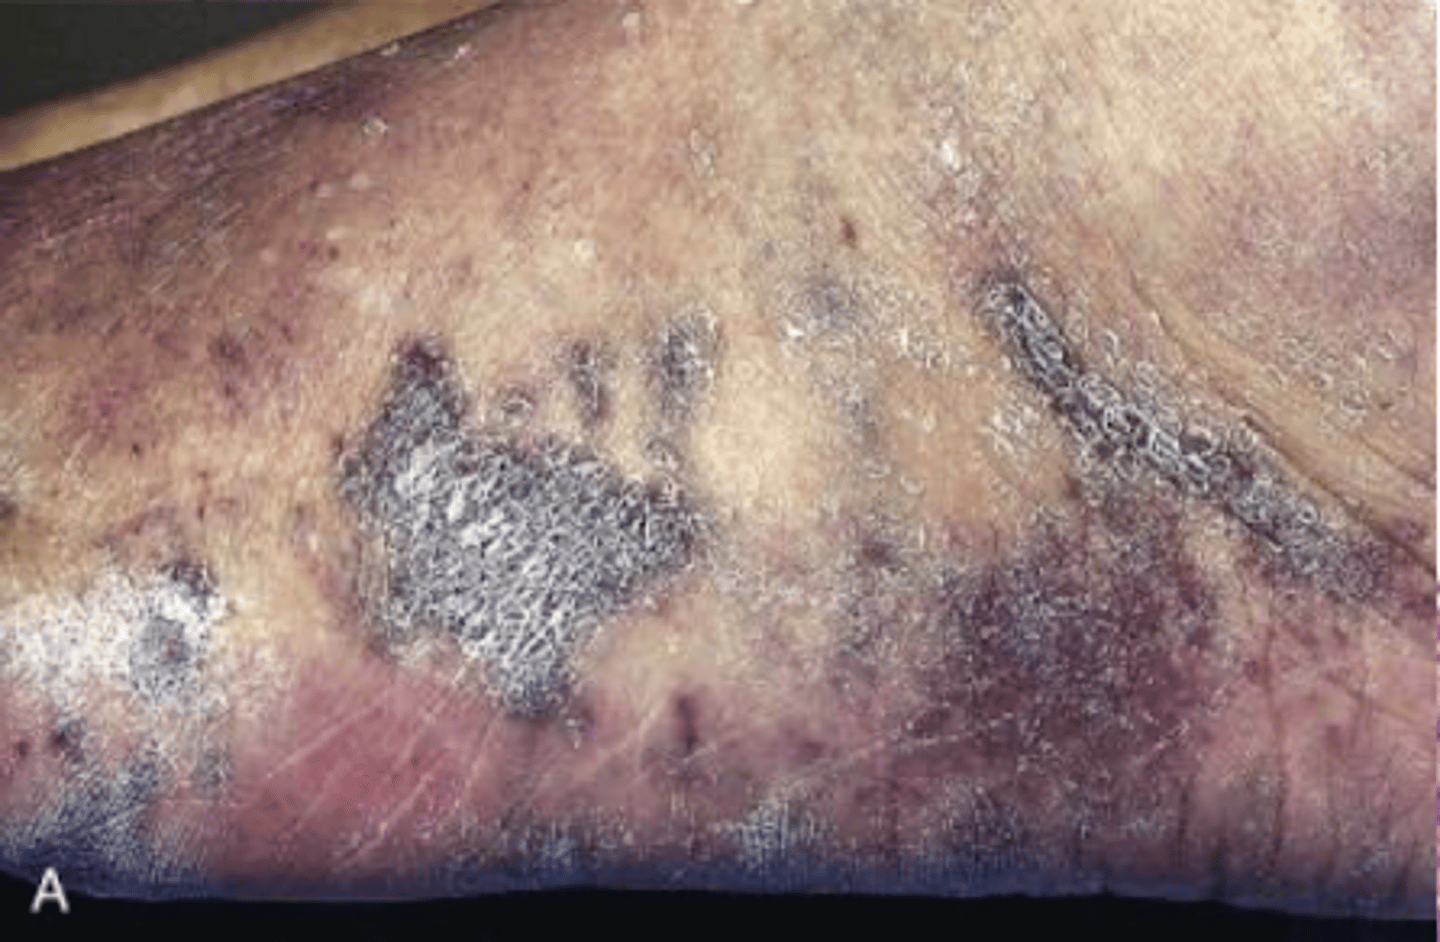

kaposi sarcoma

vascular neoplasm caused by HHV-8

s/s of kaposi sarcoma

3 stages of cutaneous lesions in LE

1. patches

2. raised plaques

3. nodular

classic KS

older men of mediterranean, middle eastern or eastern European descent

red-purple skin plaques on distal LE

AIDS-associated KS

most common HIV related malignant worldwide